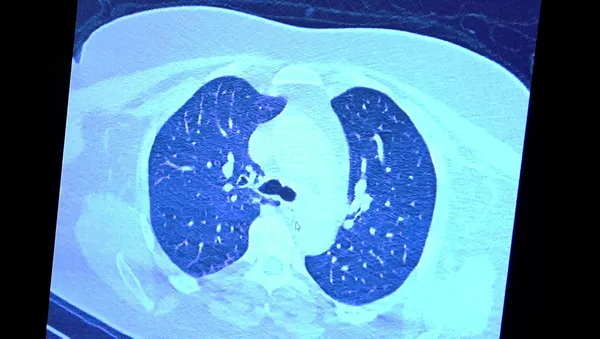

Tomografide akciğerlerdeki tutulmanın az olduğu gözlemlendi. Akabinde aynı hastanın verilen ilaçları kullanmamış ve 1 hafta boyunca tedaviye uymamış haldeki akciğer tomografisine bakıldı. Sonuç ise ilaç kullanımının önemini ortaya çıkardı. Hastanın akciğer tomografisinde yaygın buzlu camların ve hava yollarının hava yerine ciddi şekilde sıvı ile dolduğu gözlemlendi.

Akciğer tomografisinde oluşan değişim ile ilgili bilgi veren Prof. Dr. Şevket Özkaya, "Ekranda 55 yaşında bir kadın hastamızın filmini görüyorsunuz. Bu kadın hastamız acil servisimize ateş şikâyetiyle geldi ve korona virüsünden şüphe ettik. Testini yaptığımızda ise testin sonucu pozitif geldi. Tomografi çektiğimiz zaman akciğerlerinde henüz ciddi bir tutulum görünmezken hastamız 55 yaşında olduğu için her an ilerleyebilir korkusuyla Sağlık Bakanlığımızın önerdiği ilaçları ve reçeteyi hastanemizden kendisine verdik. Hasta kendini evde karantinaya aldı fakat sonradan öğrendik ki tereddüt ettiği için ilaçlarını kullanmayarak kendini evde tedavisiz bırakmış. Yaklaşık bir hafta sonra aynı hasta acil servisimize bu sefer solunum yetmezliği şikâyetiyle geldi. Solunum yetmezliği gelişince hastanın akciğer tomografisinde 'buzlu cam' dediğimiz ve daha ileri konsolide alanların oluştuğunu gördük. Yaygın akciğer harabiyeti dediğimiz bir tablo oluşmuştu. Bu durumda hastada solunum yetmezliği olduğu için yoğun bakıma almak zorunda kaldık" dedi.